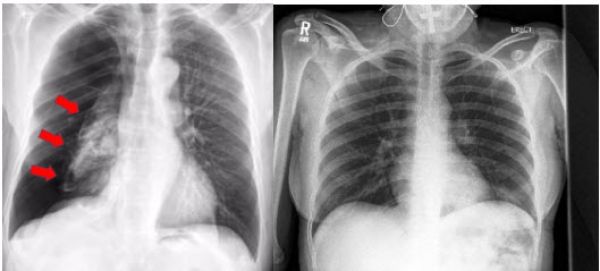

Image:  X-ray showing collapsed lung (Left) and X-ray showing a normal lung (Right).